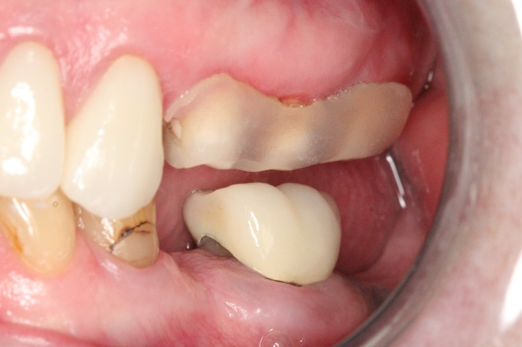

Fig 11. Preoperative healed sites.

Figure 11

Fig 12. Ceramic implants placed and sutured.

Figure 12

Fig 13. Lateral view after placement.

Figure 13

Figure 10 through Figure 13 show the preoperative x-ray and the sequence of beginning with healed sites through the surgical placement of the implants. The implants were protected by an Essix-style wound-protection removable retainer for approximately 12 weeks. After the integration phase, the implants and the natural dentition were prepared using traditional crown-and-bridge high-speed diamond and zirconia cutting burs to remove decay and existing restorative materials, to complete and refine the natural-tooth structures to receive full-crown coverage, and to prepare and refine gingival margins of the zirconia implants where needed.